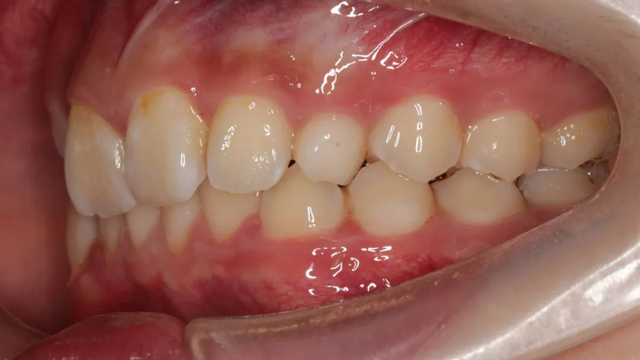

2024年9月(矫正结束后口内照)

“隐形矫正一般2-3月复诊一次,从节约时间来说很受家长青睐,但前提是小朋友要有很好的依从性,这是获得满意效果的前提。案例中的这个小朋友和家长与医生的配合度非常高,这也是我们能治疗成功的必要因素。”